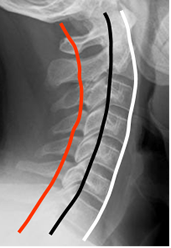

La alineación de la columna cervical en la proyección lateral, se determina trazando las líneas arcuatas. Son la vertebral anterior, vertebral posterior y la espinolaminar. (10).

(Fig 12).

Fig 12. Líneas arcuatas.

Rx lateral. Línea vertebral anterior. (Blanca), vertebral posterior (Negra) y espinolaminar (Roja).